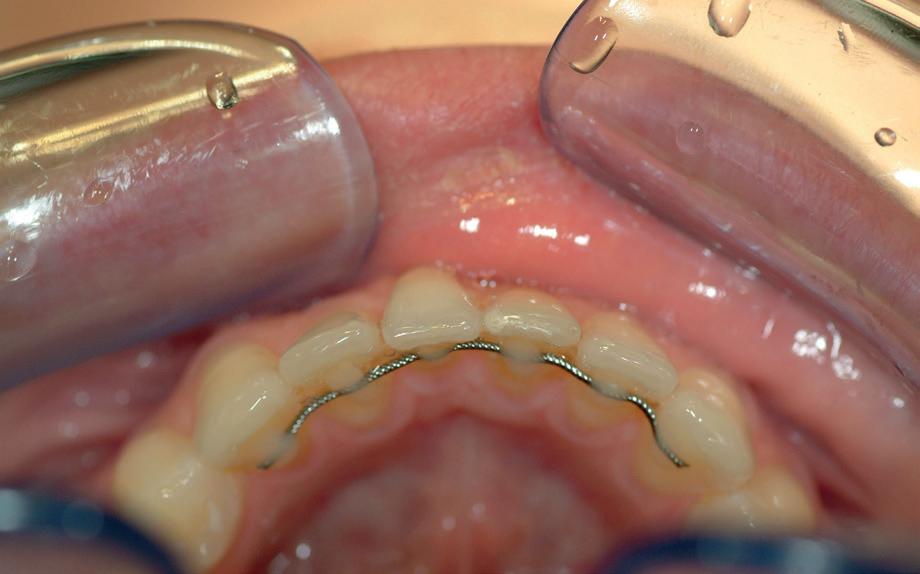

Retentie en het verborgen gevaar

De bonded retainer speelt een centrale rol in deze

2. Occlusale opname onderfront: standswijzigingen bij de 32 en de

31 door een geactiveerde retentie draad.

3. (Lokale) orthodontie leidt tot adequate standscorrectie met afname van de gingivarecessie bij de 31

problematiek. Hoewel bedoeld om stabiliteit te waarborgen, fungeert de retentiedraad bij loslating of vervorming geregeld als actieve orthodontische krachtbron. Elastic deflection of spanningsopbouw door parafunctie kan ongecontroleerde bewegingen veroorzaken waarbij tanden letterlijk “schommelen” rond een verstoorde as. Het gevolg: wortels die buccaal of linguaal buiten de botbegrenzing worden gedrukt met parodontale schade als gevolg.

Diagnostiek en preventie

Om torque-gerelateerde schade te voorkomen, is zorgvuldige diagnostiek vooraf én gedurende de retentiefase essentieel. De volgende maatregelen zijn aan te raden:

• Beoordeel de botdikte en gingivale biotype met behulp van CBCT en parodontale sonde.

• Plaats elementen altijd binnen de genetisch bepaalde botenvelop. Vermijd overmatige labiale/linguale verplaatsing, zeker bij smalle alveolaire processen. Controleer retentiedraden frequent op passiviteit en vervorming.

• Documenteer stand en gingivaniveau met regelmatige intraorale kleurenfoto’s.

5. Adequate positie onderfrontelementen met de juiste as-richting in de biologische envelop.